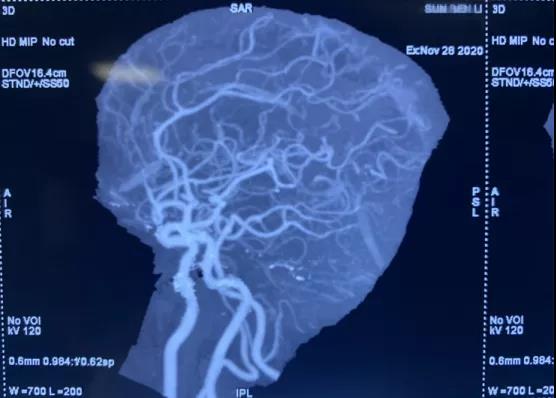

動脈瘤診斷金標(biāo)準(zhǔn)為:數(shù)字減影血管造影(DSA) ,于學(xué)利主任親自把關(guān),盛國良、楊德森等神經(jīng)外科醫(yī)師立刻以頭部CTA為基礎(chǔ),急診行顱內(nèi)血管造影術(shù),術(shù)中明確了動脈瘤的形態(tài)、大小、指向、周圍臨近血管關(guān)系。

我院神經(jīng)外科專家明確診斷后第一時間聯(lián)系與我院展開密切合作的深圳博謙醫(yī)療集團(tuán)的專家團(tuán)隊進(jìn)行遠(yuǎn)程會診,交流了影像學(xué)資料,經(jīng)過遠(yuǎn)程會診以及專家查房后制定了手術(shù)方案,獲得家屬同意后,行顱內(nèi)動脈瘤支架輔助栓塞術(shù)。